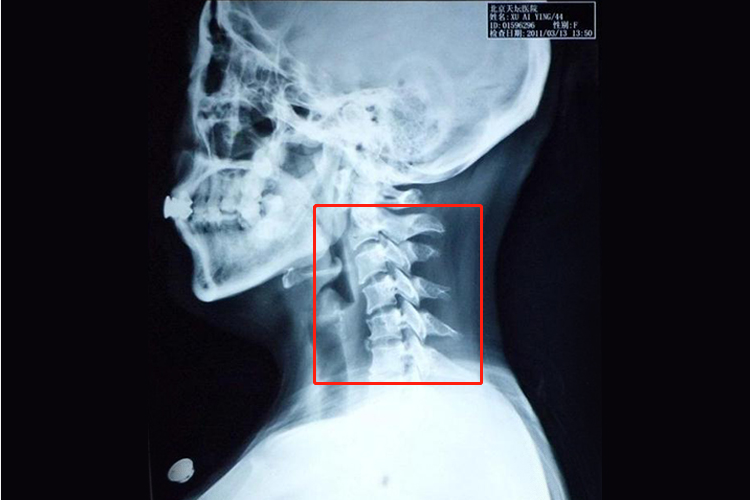

颈椎3456突出,即颈椎的第3、4、5、6节椎间盘突出,是一种常见的颈椎疾病,可能导致颈部疼痛、僵硬、活动受限,甚至影响上肢的感觉和运动功能。针对这一病症,治疗效果的好坏往往取决于病情的严重程度、个体差异以及治疗方法的选择,常见治疗为保守治疗、药物治疗等。